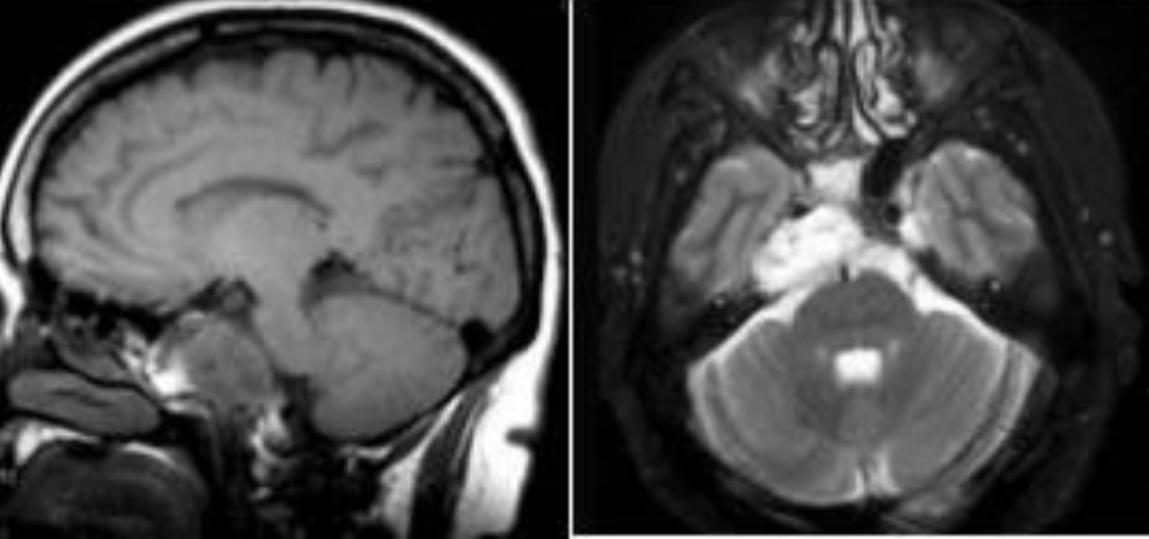

患者40+岁,女性,患者临床症状明显,近1年多来相继头痛、复视、肢体无力、吞咽困难等,当地医院诊断为较大斜坡脑膜瘤,辗转多地医院均告知肿瘤无法全切,术后并发症风险发生率高,后慕名咨询德国国际神经科学中心INI寻求巴特朗菲手术治疗,肿瘤切除97%以上,无相关手术并发症。

术前MR示:斜坡较大脑膜瘤,压迫脑干、颅神经,侵犯基底动脉等

术后MR显示:肿瘤近全切除,术后未见脑血肿、脑水肿,神经血管、脑干等组织保护完好。